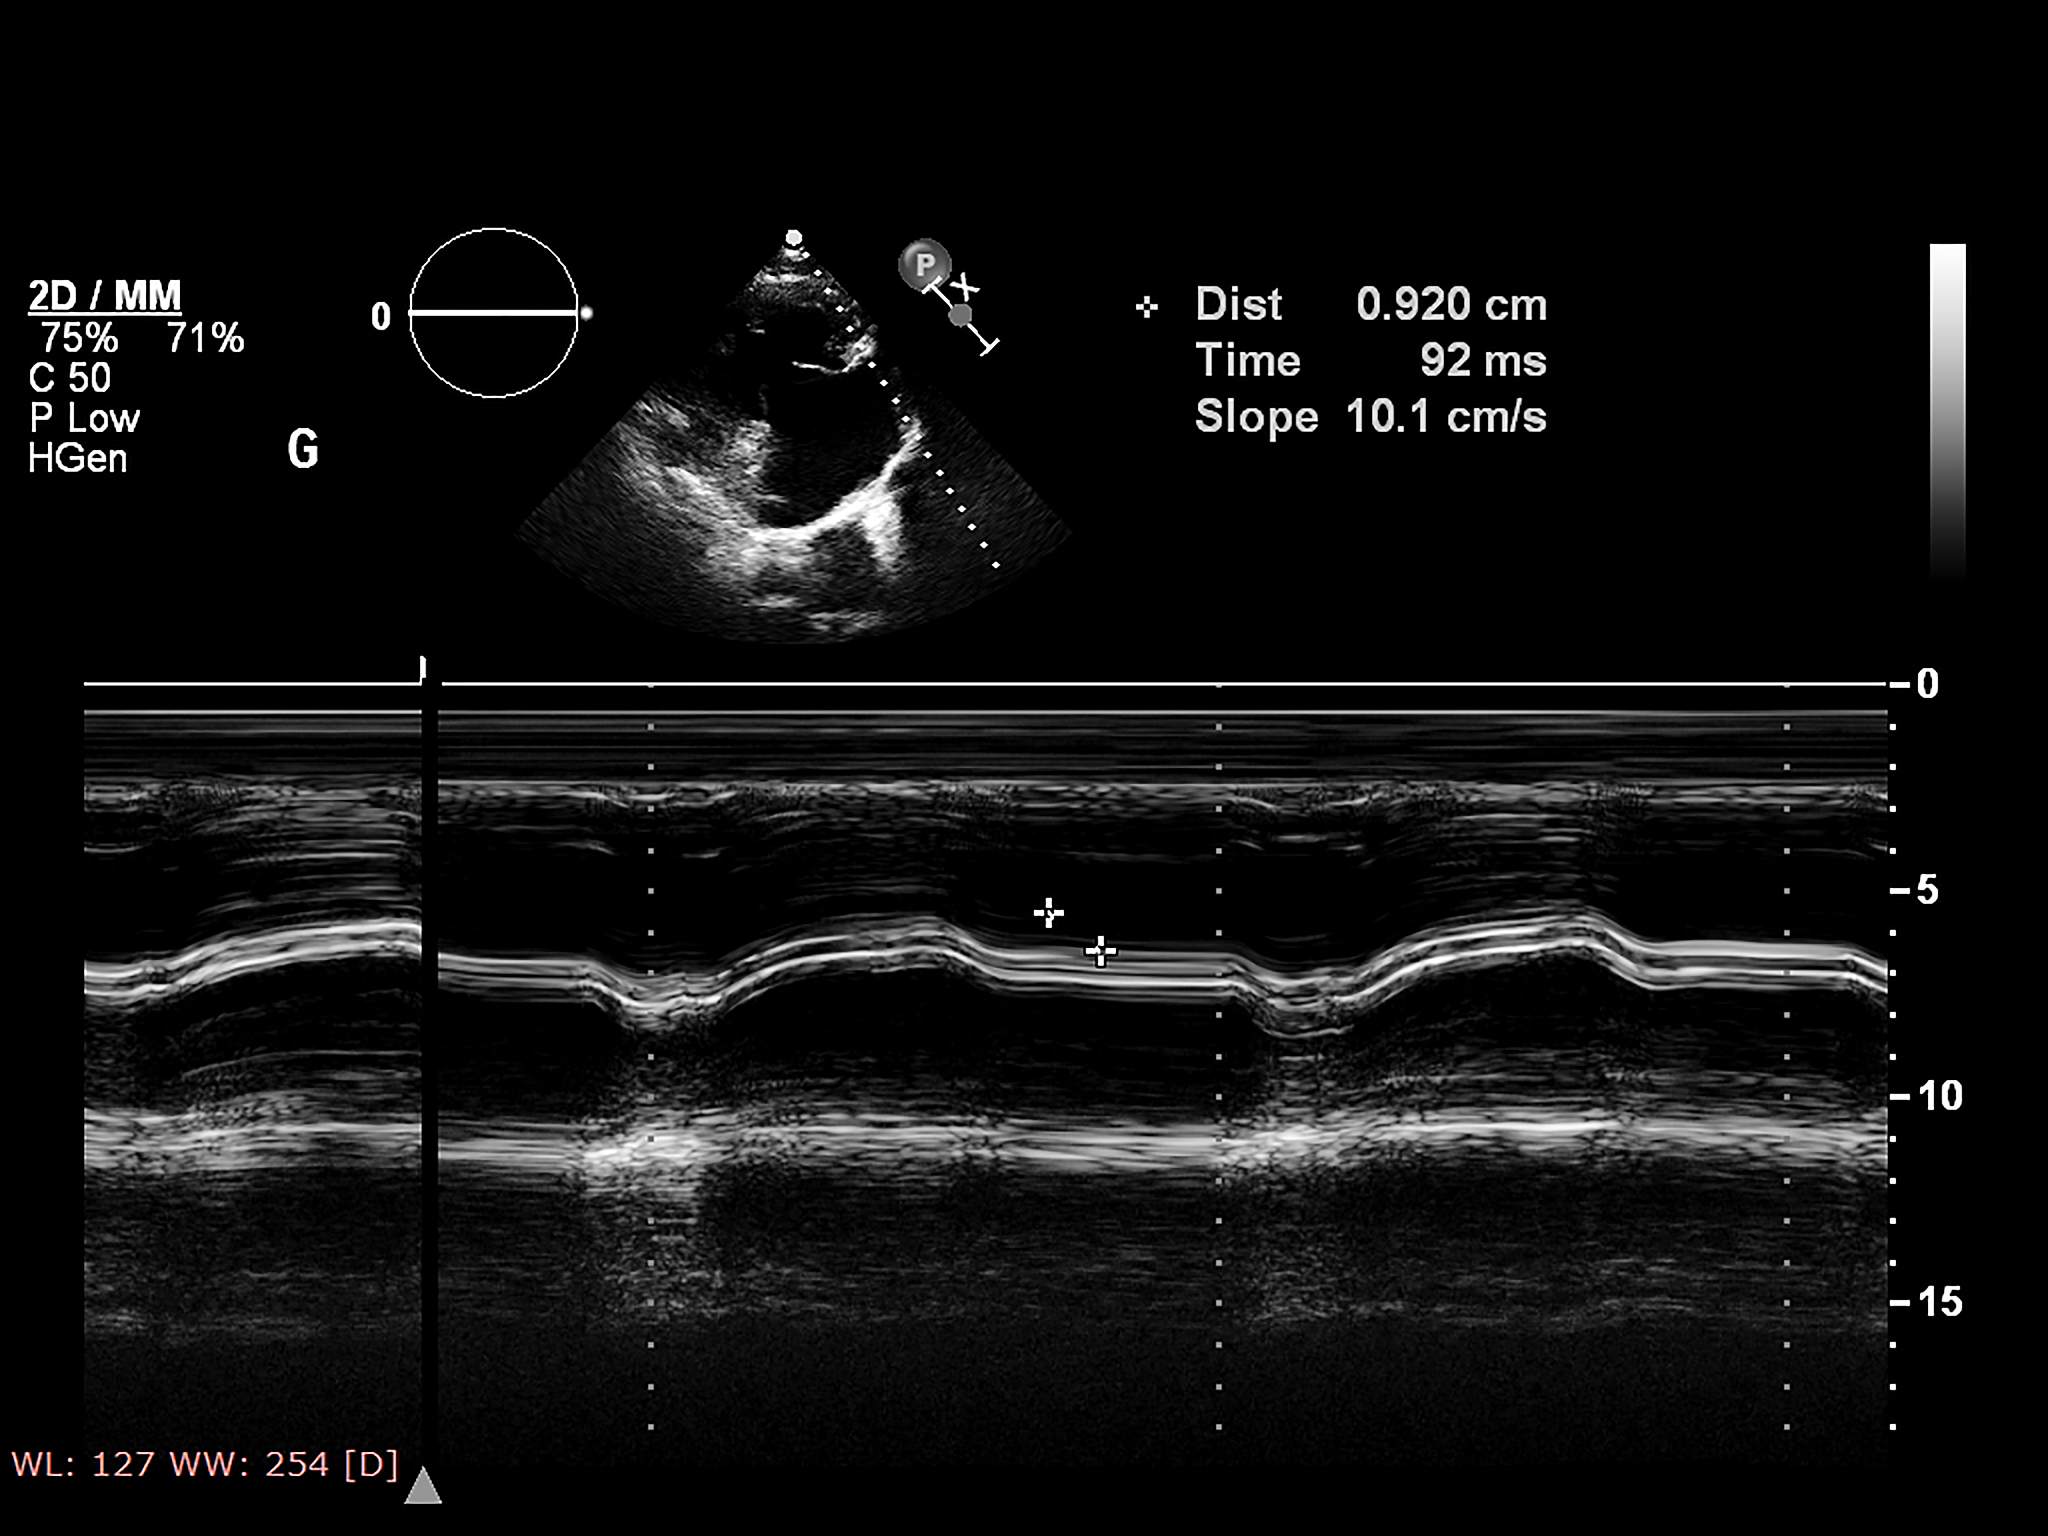

颈动脉是位于颈部两侧的主要血管,负责将血液从心脏输送到大脑。颈动脉超声是一种无痛、无创的影像学检查,利用声波来创建颈动脉图像。这项检查可以帮助医生:

• **检测颈动脉斑块堆积:*斑块是脂肪、胆固醇和其他物质在动脉壁上的堆积,会导致动脉狭窄或阻塞。 **评估颈动脉狭窄程度:*颈动脉狭窄会减少流向大脑的血液,增加中风的风险。 **监测已知颈动脉狭窄的进展:**定期进行颈动脉超声检查可以帮助医生监测病情变化并调整治疗方案。